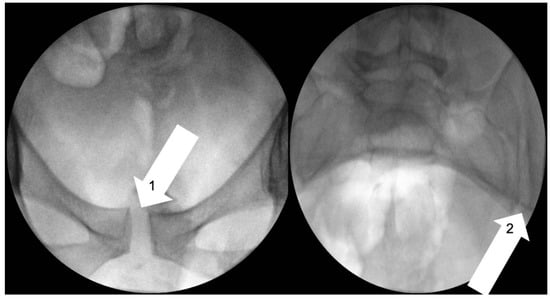

- Vleeming, A.; Albert, H.B.; Östgaard, H.C.; Sturesson, B.; Stuge, B. European guidelines for the diagnosis and treatment of pelvic girdle pain. Eur. Spine J. 2008, 17, 794–819. [Google Scholar] [CrossRef]

- Ando, F.; Ohashi, K. Using the posterior pelvic pain provocation test in pregnant Japanese women. Nurs. Health Sci. 2009, 11, 3–9. [Google Scholar] [CrossRef]

- Mens, J.M.; Vleeming, A.; Snijders, C.J.; Ronchetti, I.; Stam, H.J. Reliability and validity of hip adduction strength to measure disease severity in posterior pelvic pain since pregnancy. Spine 2002, 27, 1674–1679. [Google Scholar] [CrossRef]

- Ostgaard, H.C.; Zetherström, G.; Roos-Hansson, E. The posterior pelvic pain provocation test in pregnant women. Eur. Spine J. 1994, 3, 258–260. [Google Scholar] [CrossRef]